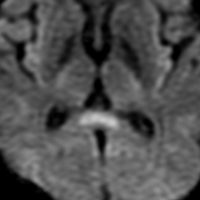

てんかんの薬を止めた時のMERS

mild encephalitis/encephalopathy with a reversible isolated SCC (splenium) lesionといいます。グリオーマの患者さんで予防的に抗てんかん薬を処方することは多いです。腫瘍が落ち着いて長くてんかん発作がない時には,抗てんかん薬を中断します。その時に,MRIで脳梁膨大部 splenium というところに異常な初見が出てグリオーマの再発と間違うことがあります。でもこれはMERSという一時的な病変で,何もしないでも消失します。

左が拡散強調画像 DWIで脳梁膨大部が高信号で白く見えます。右はFLAIR画像でよく見るとちょっとだけ白く見えます。この例はとても軽い初見でDWIでしかはっきりしませんが,通常はFLAIR画像で楕円形の病変としてみられます。

間脳下垂体障害で低ナトリウム血症になると,MERSが生じることもあります。